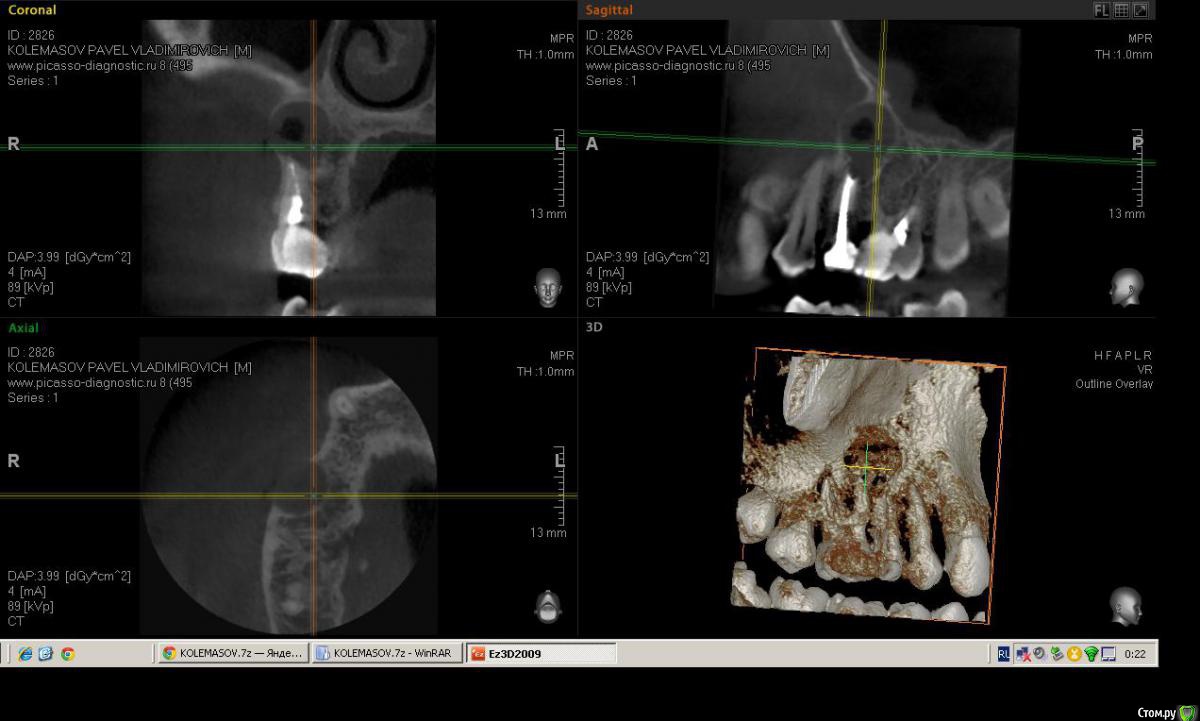

Salma Опубликовано 14 февраля, 2015 Поделиться Опубликовано 14 февраля, 2015 Пациент пришел с ноющими жалобами в области верхней челюсти справа, спасался обезболивающим несколько дней, говорит периодически болит, но сейчас разболелось сильно. Записался на вечер, на прием уже пришел немного припухшим. В полости рта, 16 зуб с глубокой полостью, перкуссия слабоболезненна, отечность болезненность по переходной, при надавливании выделяется гной, на небе в проекции верхушки небного корня тоже как бы формирующийся свищ с отделяемым. Делаем снимок прицельный, вижу разрежение в области 5-ки ( по словам пациента лечен более 10 лет назад). ДОговариваемся, что сегодня снимаем острую боль, а далее пациент делает кт и определяемся с судьбой зубов.Анестиеия, мех, мед,кальций. Делаю поласбляющий разрез, гной, нехило так проваливаюсь, кюретаж, дренаж. Собственно кт: (могу выслать ссылку на почту с кт) Ссылка на комментарий